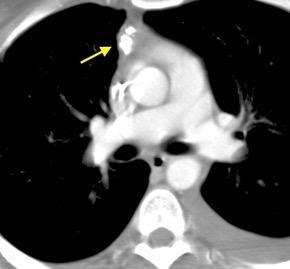

99.GANGLIOS CON HIPERCAPTACIÓN TRAS

CONTRASTE